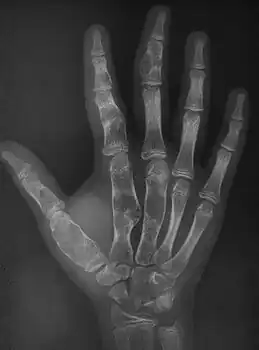

X-ray wrist: Ollier disease in child

X-ray hand:Ollier disease in child